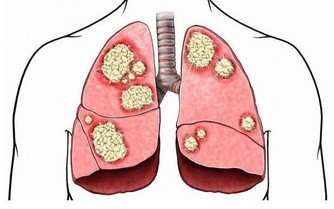

8. 你的呼吸急促

硒蛋白的另一個重要的工作是保護你的心臟,有人甚至因為缺硒導致心臟衰竭。

但是,雖然良好的硒水平與健康密切有關,你也不應該馬上跑出去補充硒片,

因為如果你服用多種維生素和硒補充劑,很容易過量,這可能導致硒中毒。